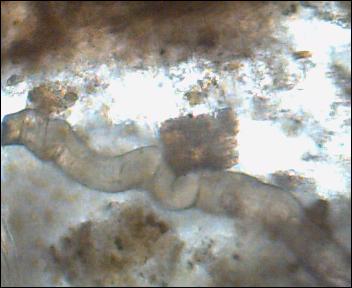

Ta duża gruba glista to wg mnie może być człon tasiemca (wyrażnie widać oderwania). Były równiez wiciowce i 2 inne stworki. Co do stworków, to nie mam pewności co to jest.

- pow 200 x

człon tasiemca? nie ruszało się to to - Obraz 001.jpg (16.9 KiB) Przejrzano 2806 razy